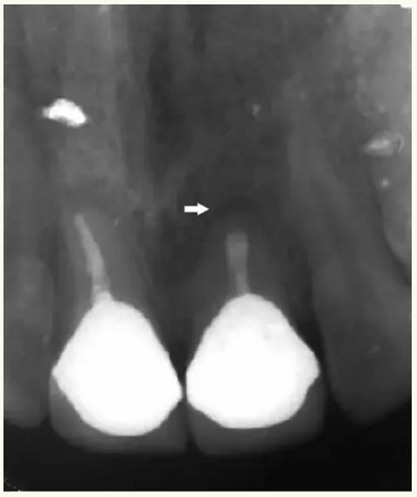

▲21牙根近中側(cè)位于根尖1/3和根中1/3交界處有牙周膜間隙略增寬

▲術(shù)后,X線顯示:21根尖切除區(qū)域骨質(zhì)修復(fù),根管倒充填物完好,原牙周膜間隙增寬影消失